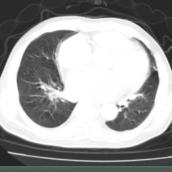

2月25日二诊:患者精神一般,少许气促症状,活动后加重,仍有心慌心悸,口干口苦,心率58次/min,血氧饱和度99%。肢体肤温改善,舌暗红,苔薄白,脉缓沉细。胸部CT提示双肺可见多发磨玻璃密度影,双侧胸膜不厚,左上肺可见少许纤维斑片影,双侧胸腔未见积液征象(图2-7-14)。

图2-7-14 2020年2月25日胸部CT